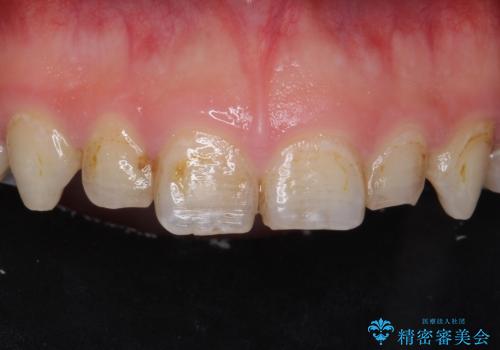

[セラミック治療] 前歯の見た目をきれいにしたい

担当医 大元洋佑

![[セラミック治療] 前歯の見た目をきれいにしたいの症例 治療前](https://seimitsushinbi.jp/wp/wp-content/uploads/2021/06/968e750651facb819c8d4d824a831cd9-500x350.jpg?v=1622871753)